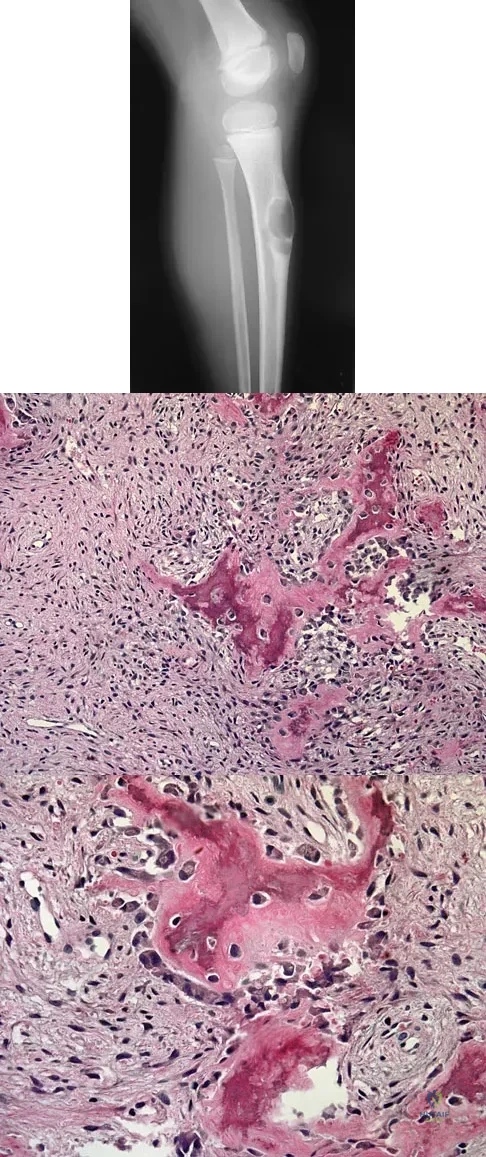

An 83-year-old woman reports pain in her left middle finger after a minor injury. Laboratory studies show a WBC count of 7,000/mm3, an erythrocyte sedimentation rate of 3 mm/h, a uric acid of 10.4 mg/dL, and a normal serum protein electrophoresis. Radiographs are shown in Figures 49a and 49b. A core biopsy specimen is shown is Figure 49c. In addition to treatment of the finger fracture, treatment should include

This clinical picture is most consistent with periarticular erosions from gout. The patient has multiple periarticular lytic lesions in the hand. The laboratory studies show an elevated serum uric acid level, and the biopsy specimen demonstrates acute and chronic inflammation with prominent clefts. Therefore, the preferred treatment is systemic control of her gout. Radiation therapy, chemotherapy, and/or amputation should be considered for a malignancy; however, the pathology does not demonstrate any evidence of pleomorphism, high nuclear-to-cytoplasmic ratio, nuclear atypia, or mitotic activity. Antibiotics for an infectious process is a consideration, but the minimal elevation in the WBC count and erythrocyte sedimentation rate does not support an infectious process. Wise CM: Crystal-associated arthritis in the elderly. Clin Geriatr Med 2005;21:491-511.